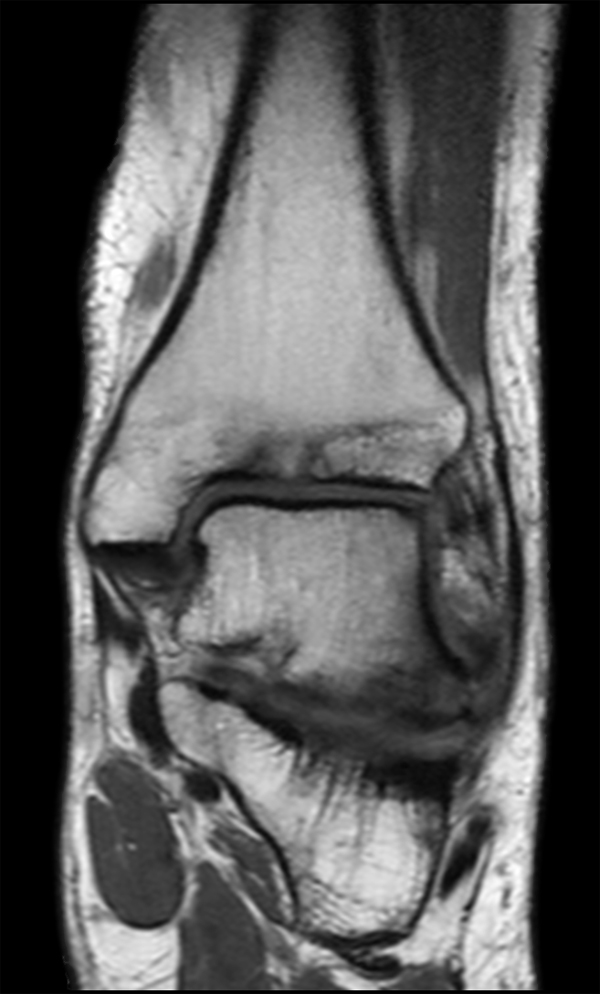

Coronal T1w TSE